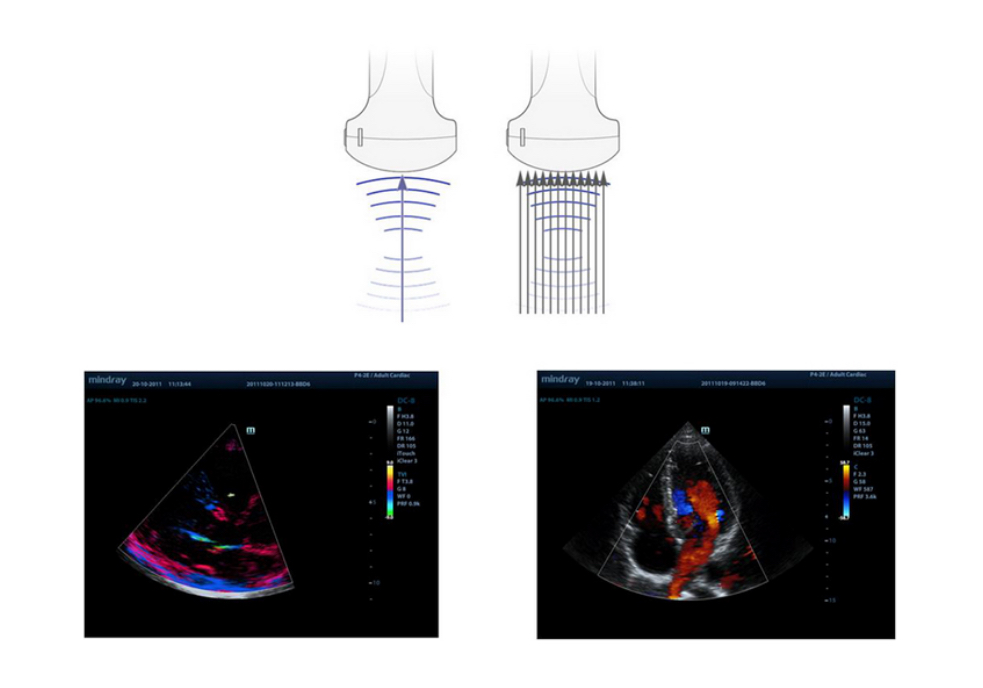

Echo-enriched Beam Forming

Echo-enriched beam former permits the use of traditionally neglected echo signals of adjacent beams to form one finer and stronger imaging beam, providing better ŌĆśout-of-focusŌĆÖ image resolution and deeper image penetration.

Multi-Beam Formation

Maximum 12 times tasking for one transmitted beam, resulting in excellent time resolution and higher frame rate.